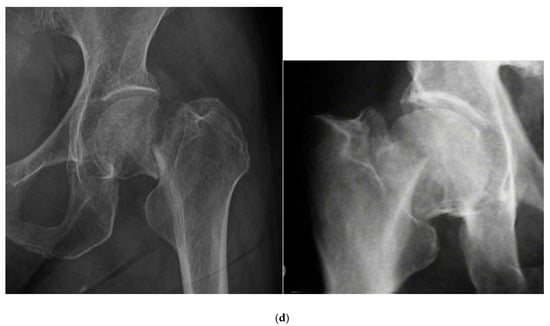

2.1. Classification of Femoral Neck Fractures

- Stage I: incomplete fracture; nondisplaced, valgus impacted

- Stage II: complete fracture; nondisplaced

- Stage III: complete fracture; partially displaced

- Stage IV: complete fracture; fully displaced